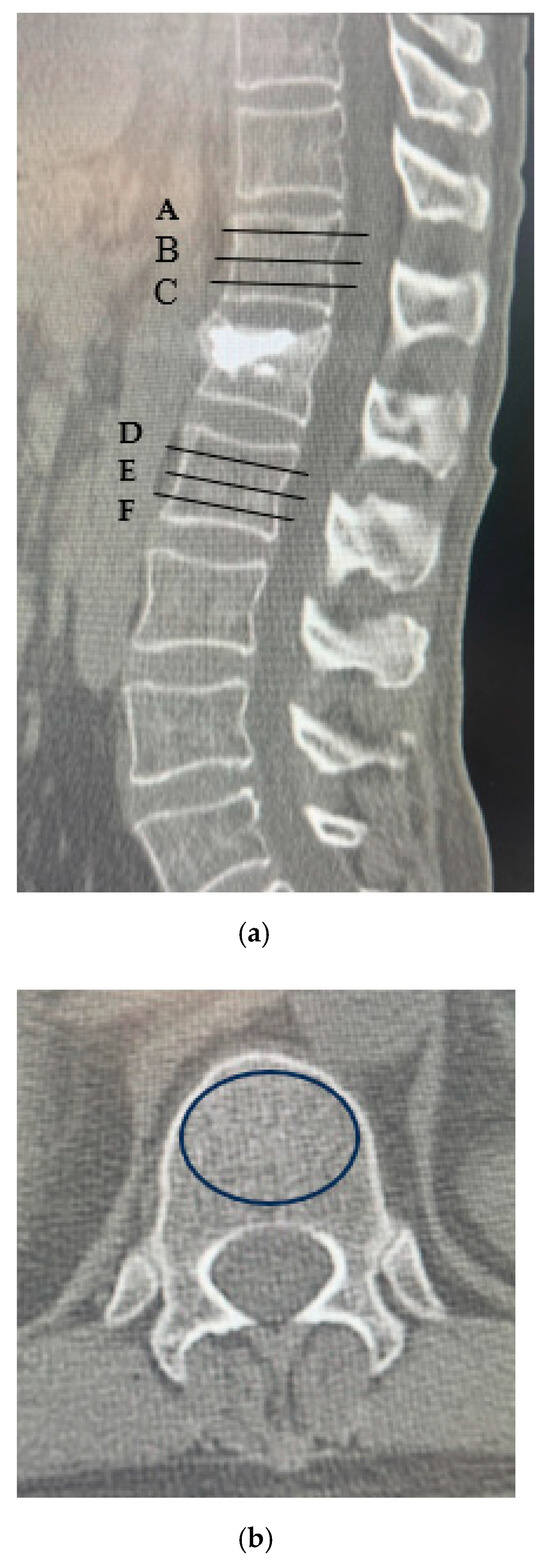

| A | 53.6 ± 68.9 | 94.0 ± 79.5 | p < 0.05 |

| B | 57.3 ± 72.3 | 76.7 ± 81.0 | p < 0.05 |

| C | 62.9 ± 67.2 | 86.2 ± 76.2 | p < 0.05 |

| D | 50.7 ± 69.7 | 94.3 ± 79.6 | p < 0.05 |

| E | 46.8 ± 71.2 | 72.2 ± 85.7 | p < 0.05 |

| F | 47.9 ± 68.1 | 83.0 ± 83.4 | p < 0.05 |

| Upper vertebral CT values (A + B + C/3) | 61.1 ± 6.03 | 84.7 ± 2.75 | p < 0.05 |

| Lower vertebral CT values (D + E + F/3) | 51.5 ± 8.44 | 81.0 ± 3.85 | p < 0.05 |